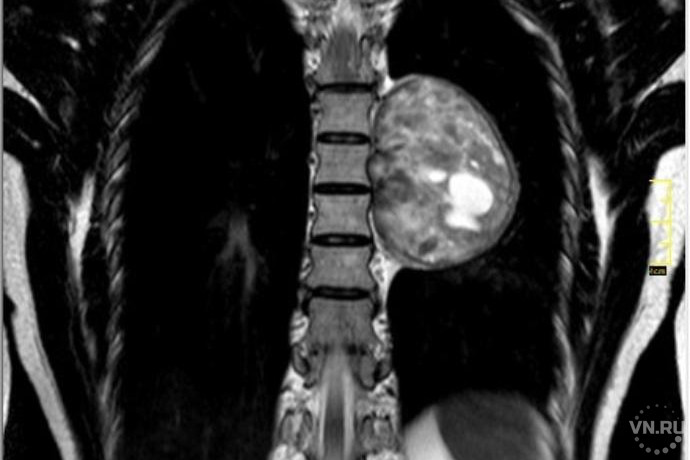

«В результате МСКТ выявлено гигантское объёмное образование, размером с мужской кулак, - говорит врач-нейрохирург, кандидат медицинских наук Игорь Васильев. - Невринома располагалась в плевральной полости непосредственной близости к позвоночному столбу и аорте, на уровне Th 5-Th 7 грудных позвонков. Далее мы провели дообследование в объёме МРТ и МСКТ грудного отдела с контрастным усилением для визуализации сосудистых структур и аорты в частности, которые могут быть вовлечены и питать данное образование».

Невриомы обычно располагаются в позвоночном канале, воздействуя на спинной мозг, а не растут из нервных структур. Врачи называют такие опухоли «песочными часами».